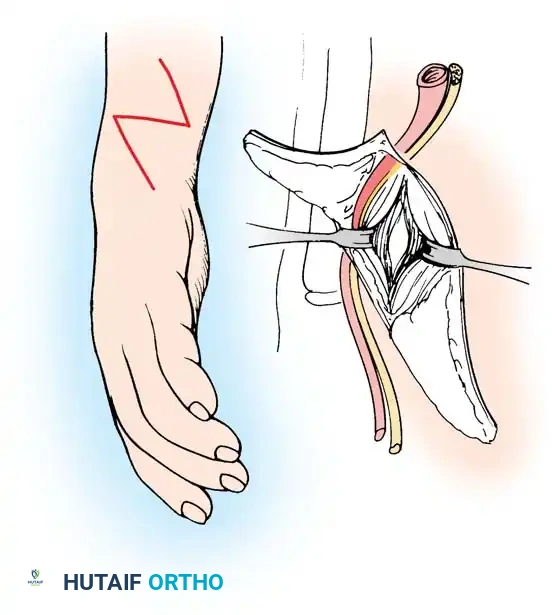

A newborn presenting with a transverse deficiency typically exhibits a slightly bulbous, well-padded stump. In more distal deficiencies, rudimentary, vestigial digital "nubbins" are frequently observed.

Fig. 76-2 Failure of formation (digital nubbins). The presence of functional wrist motion allows the limb to be used effectively as an assisting hand.

Hypoplasia of the more proximal musculature is a key clinical finding that helps differentiate true transverse deficiencies from amputations caused by congenital constriction band syndrome (amniotic band sequence). In the most common presentation—the upper forearm amputation—the forearm is usually no more than 7 cm long at birth and will reach a maximum length of approximately 10 cm by skeletal maturity.

In midcarpal amputations (the second most frequent level), the rudimentary digital remnants are almost always nonfunctional. However, because the radiocarpal joint is preserved, pronation and supination are usually possible, providing a highly functional assisting limb. Cognitive development and intelligence in these children are generally normal.